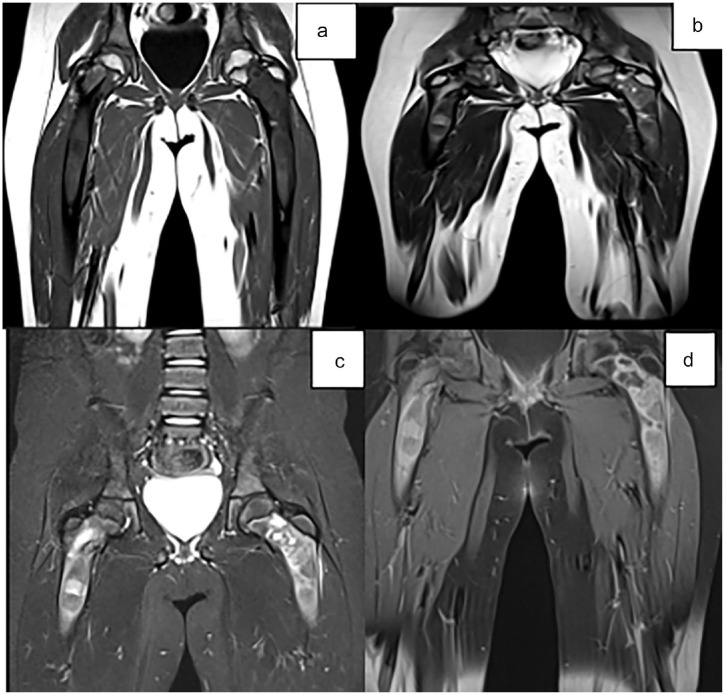

纤维发育不良是一种罕见的非遗传性先天性疾病,主要有两种形式:单相和多相。单恒定型较为常见,而多恒定型通常伴有综合征,较为罕见。本病例涉及一名 10 岁的患者,他被诊断为多发性纤维发育不良并伴有内分泌病。本报告根据患者的病例,从临床和放射学方面探讨了这种疾病。

Fibrous dysplasia is a rare non-hereditary congenital condition characterized by 2 main forms: monostotic and polyostotic. Monostotic is the more common form, while polyostotic, often associated with a syndrome, is rarer. The case presented involves a 10-year-old patient who was diagnosed with polyostotic fibrous dysplasia accompanied by an endocrinopathy. This report explores the clinical and radiological aspects of this condition based on the patient's case.